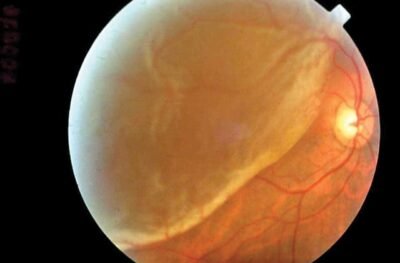

3. Retinal Detachment

As mentioned earlier the retina is not a single layered structure but made up of 10 layers. When part of the layers gets pulled away from its normal position it is called retinal detachment. If you have any of the following symptoms, you need urgent consultation with your ophthalmologist.

- Sudden flashes of light

- Many new floaters

- Shadow or curtain over vision

Retinal detachment requires surgery to keep the retina in its original position.